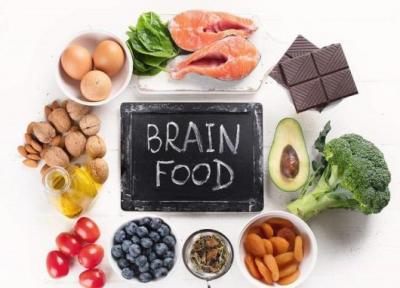

بهترین و بدترین مواد غذایی برای تقویت مغز

همه ما می دانیم که مغز مهم ترین اندام بدن است و عملکردهای مهمی به عهده دارد. به همین دلیل است که تقویت مغز و نگه داشتن آن در شرایط بهینه از طریق مصرف مواد غذایی سالم ضروری است. بعضی از خوراکی ها برای مغز مفید هستند و به عملکرد بهتر آن کمک می کنند. این در حالی...